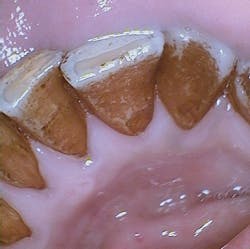

The patient in the image appearing with this column is scaled every four months because of the heavy stain on his teeth. Since he is a professional, he is very cognizant of his appearance when meeting with clients and makes certain that he arrives for his scheduled appointments.

George has stain on his teeth due to the fact that he drinks Darjeeling tea throughout the day, usually five to seven cups of strong tea. Darjeeling tea is highly flavored and is a favorite type of tea in India. It is often used in Chai tea that is popular in the United States as well.